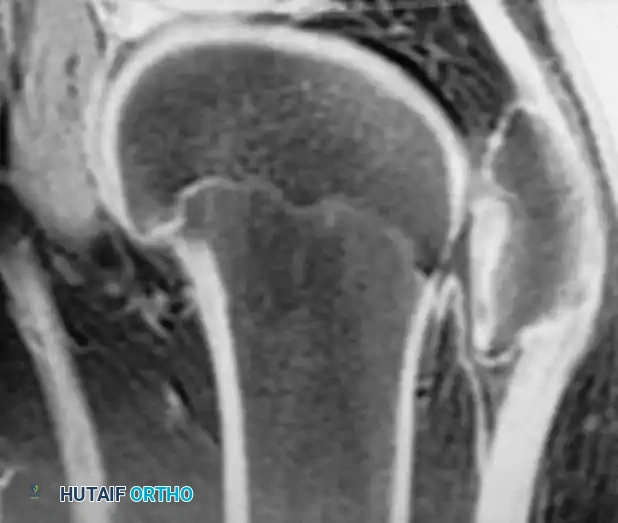

Osteochondritis dissecans (OCD) of the ankle primarily affects the talar dome. The natural history of this lesion in children with open physes is highly favorable compared to adult populations.

Natural History and Imaging

Bauer et al., in a long-term follow-up study (≥ 20 years) of 30 children with ankle osteochondritis, found that only one patient developed severe osteoarthritis. The vast majority experienced complete healing with only minor residual radiographic changes. This is in stark contrast to osteochondritis of the knee, where secondary osteoarthritis is a frequent complication.

Radiographic and MRI evaluation of osteochondral lesions of the talar dome, demonstrating subchondral separation and surrounding edema.